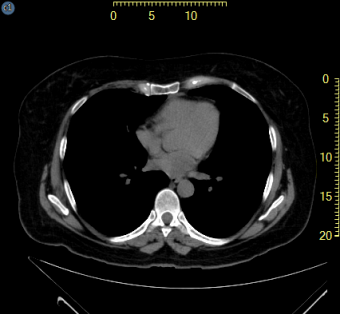

Ruler overlays appearing on the outside of the image frame exist for all calibrated images as shown highlighted in yellow below. The user is able to assign the location of the rulers, and whether they exist for the vertical, horizontal or both planes.